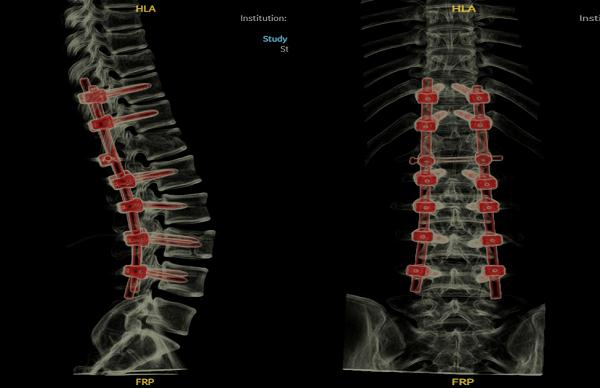

相较于传统的手术方式,该技术能够在术中实现精确定位,协助医生在患儿受伤的椎体精准置钉,从而减少内固定相关并发症,尽可能地避免椎体的疏松和不稳定,降低患儿二次损伤的几率,并大幅缩减手术时间。

术后CT示椎体内固定位置稳定,骨折端对位、对线好

最终,凭借着医生丰富的经验和精湛的技术,手术顺利完成。术后第二天,孟迪的双下肢便可自主完成上抬、屈膝等动作,且双足麻木感较此前明显好转,手术成效显著,为后续的康复治疗奠定了坚实基础。目前,孟迪正处于术后康复阶段,医院正继续予以营养神经、抗感染等对症处理,并将根据患儿恢复情况,及时调整治疗方案。